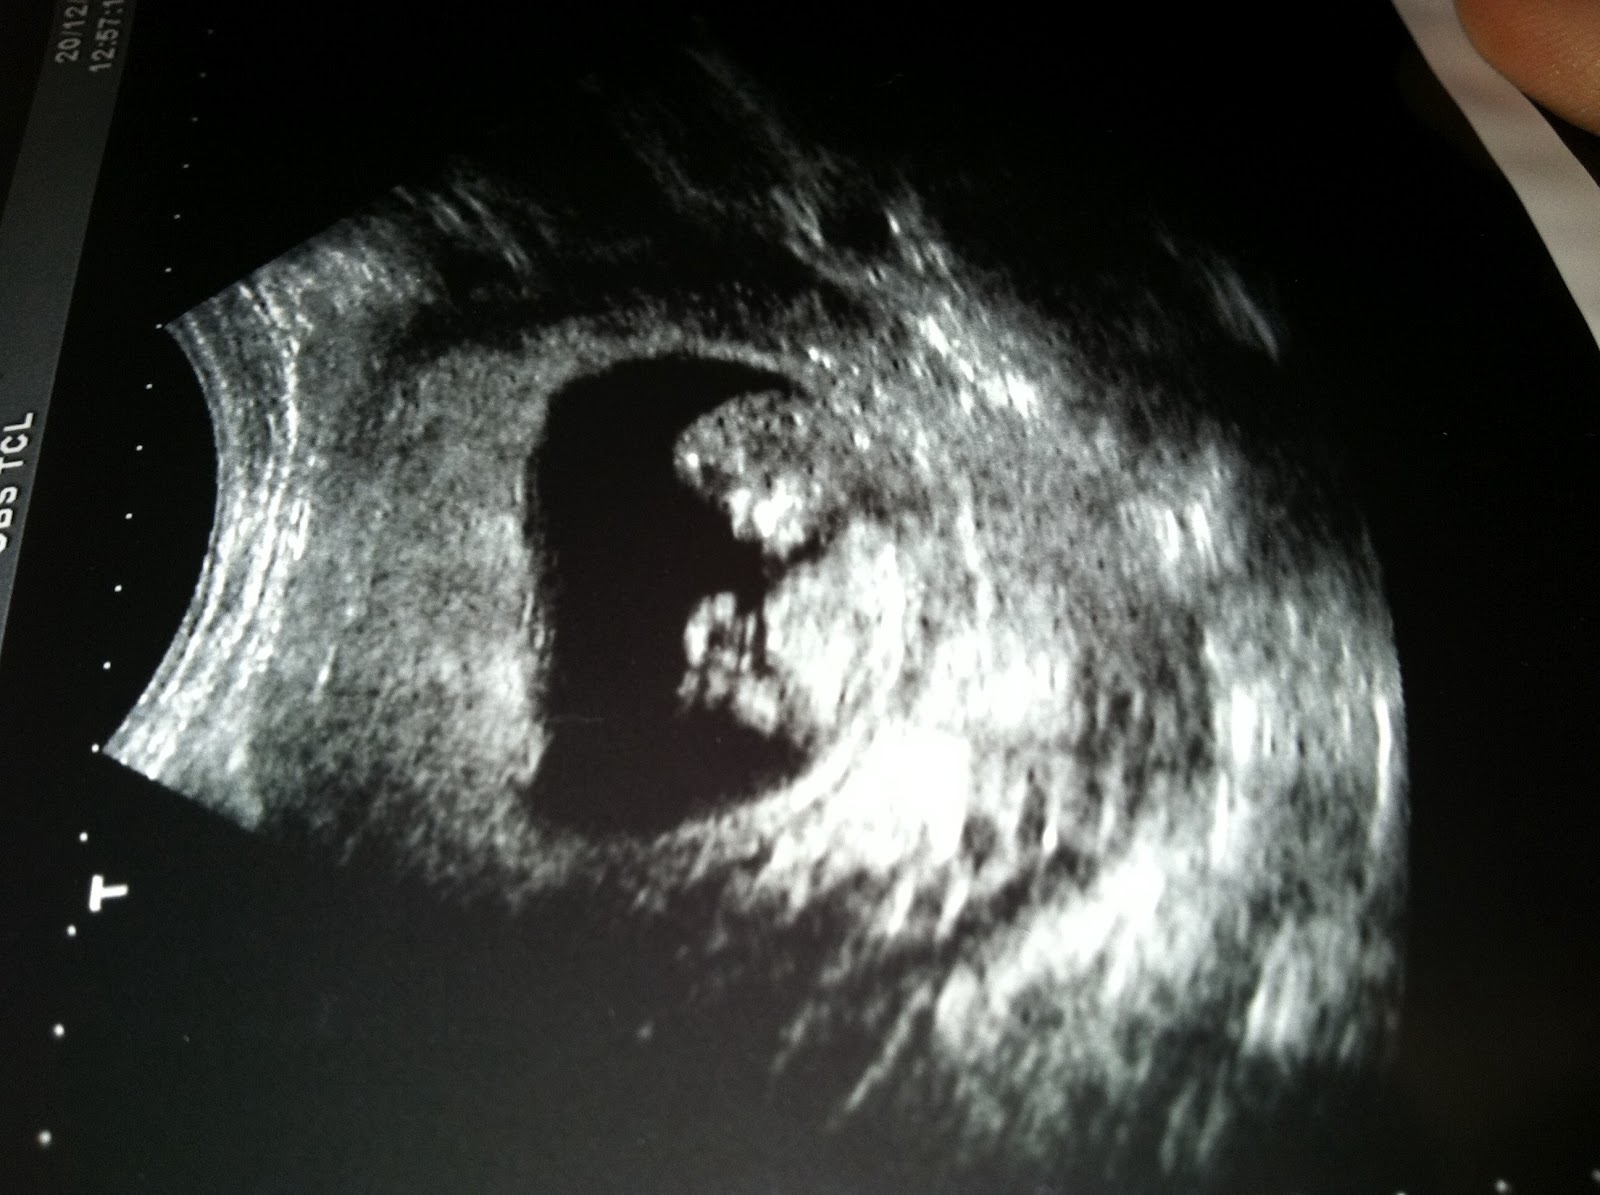

| 3 MONTH ULTRASOUND |

I'm Pregnant!

Yes, it's true.

So, I found out I was expecting baby #5 just before Christmas and then, I got sick.

By mid January, I was actually sane enough to start keeping track of what week I was in my pregnancy and now I can't believe I'm almost 6 months along!

New baby, is moving up a storm now and the whole thing amazes me, every single time.